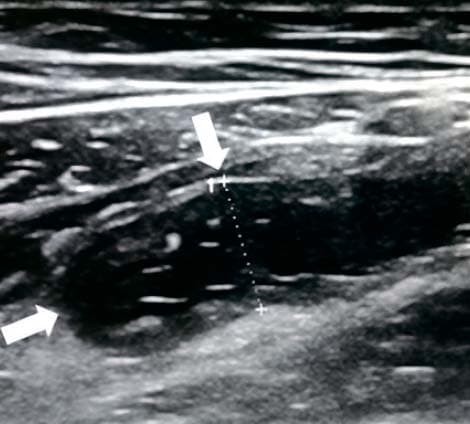

Каловые камни образуются из плотных каловых масс и неорганических солей. При УЗИ каловый камень выглядит как внутрипросветное гиперэхогенное образование с акустической тенью. Каловый камень в просвете воспаленного аппендикса часто сочетается с гангренозным аппендицитом (см. рис. 6).

Рисунок 6. Каловый камень в просвете аппендикса.